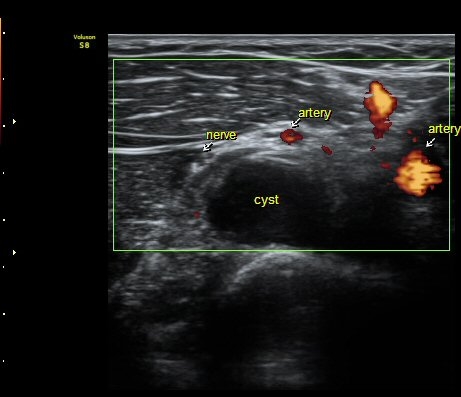

Á¶ÀýÇÏ´Ï Èİñ°ß½Å°æÀÇ Á¾´Ü¸é À̹ÌÁö°¡ °üÂûµÇ´Âµ¥ ³¶Á¾¿¡ ÀÇÇØ Ç¥ÃþÀ¸·Î ÀüÀ§µÇ¾î

ÀÖ´Ù(±×¸² 6,7). ±×¸² 8. ³¶Á¾°ú Èİñ°£½Å°æ ÁÖÀ§¾Ö¼­ °üÂûµÇ´Â µ¿¸Æ.